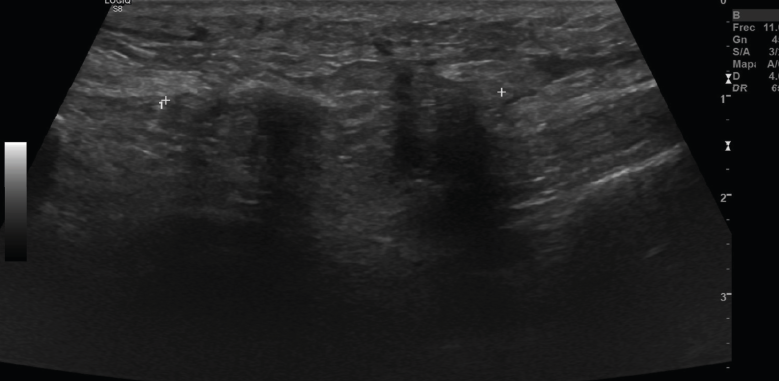

2.2. Roturas

Se observan áreas hipoecoicas de solución de continuidad de las fibras tendinosas(7), con retracción de los márgenes con la contracción muscular cuando la rotura tendinosa es completa (Figuras 9 y 10).

Figura 9. Corte sagital de una ecografía de rodilla: foco hipoecoico por rotura parcial del tendón cuadricipital.

Figura 10. Corte sagital de una ecografía de rodilla: ausencia del tendón rotuliano por rotura completa, con hematoma señalado en el trayecto del tendón.